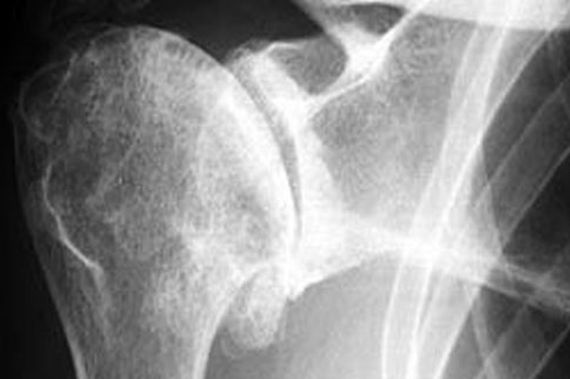

Starije žene s visokom razinom anksioznosti imaju veću vjerojatnost za lošije stanje kostiju, navodi se u studiji. Istraživači su ispitivali stupanj anksioznosti i mineralnu gustoću kostiju kod 192 žene u postmenopauzi. One s najmanjim stupnjem anksioznosti su imale 20% rizik koštanih prijeloma tijekom 10 godina, dok je kod žena s najvišim stupnjem anksioznosti ovaj rizik iznosio 25%, pokazalo je istraživanje.

Za žene s najnižom razinom anksioznosti, 10-godišnji rizik od prijeloma kuka je bio oko 7,2%, u usporedbi s 9,3% kod žena s najvišom razinom anksioznosti.